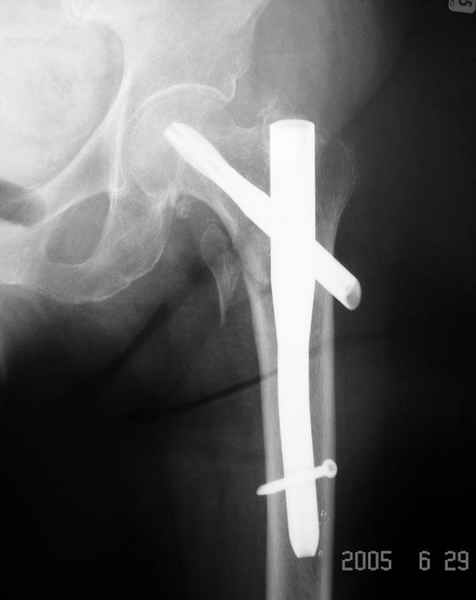

Да, сейчас это и у нас самый напрашивающийся выбор. Сделали гвоздем ChM, картинки в приложении.

У молодых реконструкционный гвоздь самое то. При остеопорозе надо что-то помассивнее.

Как раз недавно у меня был примерный случай: больному 36 лет, поступил ночью, травма в результате мотоциклетной аварии, кроме чрезвертельного и спирального перелома левого бедра имеется переломы костей предплечья с этой же стороны. Скелетное вытяжение, а на следующий день больной про оперирован на ортопедическом столе с дистракцией. Чтобы не расколоть чрезвертельный перелом провели временную спицу ближе к переднему кортексу, из малого разреза костодержатель для репозиции, а фиксацию провели антиградным штифтом. Этапы операции на снимках.